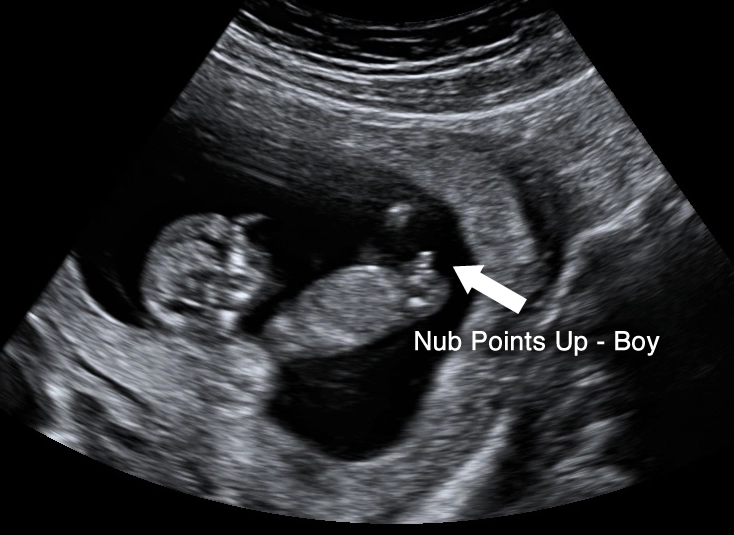

This is often the first detailed look at your baby, and it's breathtaking. The 12-week scan, sometimes combined with the First Trimester Screening (which assesses risk for chromosomal conditions), gives you a clear picture of that little occupant.

On the screen, you'll see your baby's location clearly within the amniotic sac inside the uterus. The sonographer will measure the baby from crown to rump to confirm your due date. They'll check for the presence of a nasal bone and measure the nuchal translucency—a small fluid space at the back of the baby's neck. An increased measurement can be a soft marker for certain conditions.

Beyond the medical checks, you'll get to see your baby in action. You might see the heart beating rapidly (around 120-160 beats per minute), watch the baby bring its hand to its mouth, or see it bounce gently against the uterine wall. It makes the whole thing feel wonderfully real.